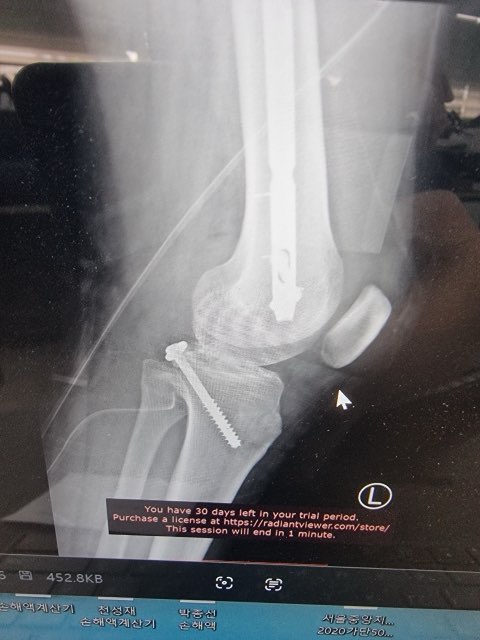

MRI, X-Ray 가지고 있는 사진 첨부했습니다.

무릎 골절, 견갑골 골절, 무릎인대 파열, 대퇴골의 골절, 경골 골절, 흉추 골절, 다발의 타박상, 다발의 찰과상, 뇌진탕